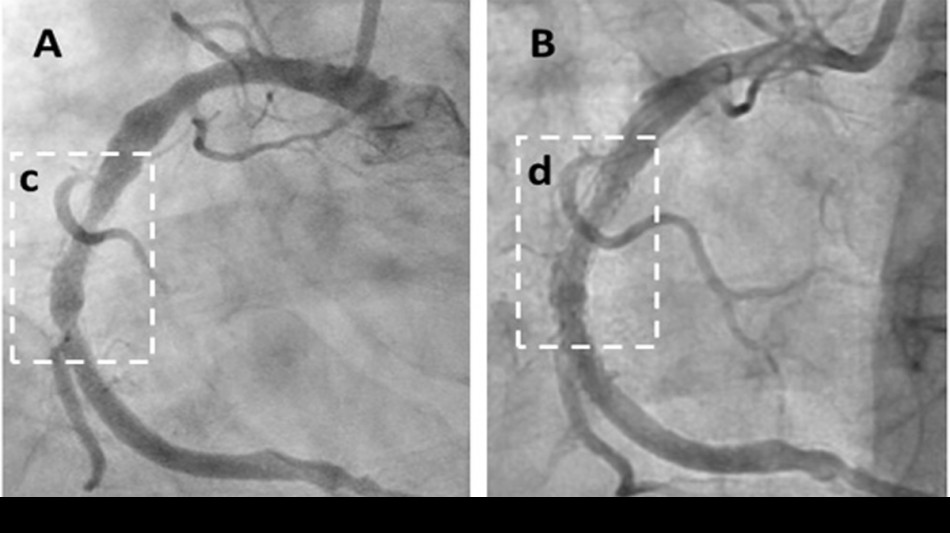

The peer-reviewed case series demonstrates rapid symptom relief and significant regression of arterial plaque, marking a potential paradigm shift in heart disease treatment. The study followed 20 high-risk patients with advanced angina, with 18 (90%) reporting substantial symptom improvement (P0.0001) compared to expected outcomes. Objective imaging confirmed unprecedented results, including Coronary Artery Calcium (CAC) score reductions (e.g., from 591 to 521) and a 70% coronary artery blockage reduced to 27%. Cavadex, formulated with 2-hydroxypropyl-β-cyclodextrin (HPβCD), stimulates the body's natural vascular repair, offering a faster, more effective approach than existing therapies.